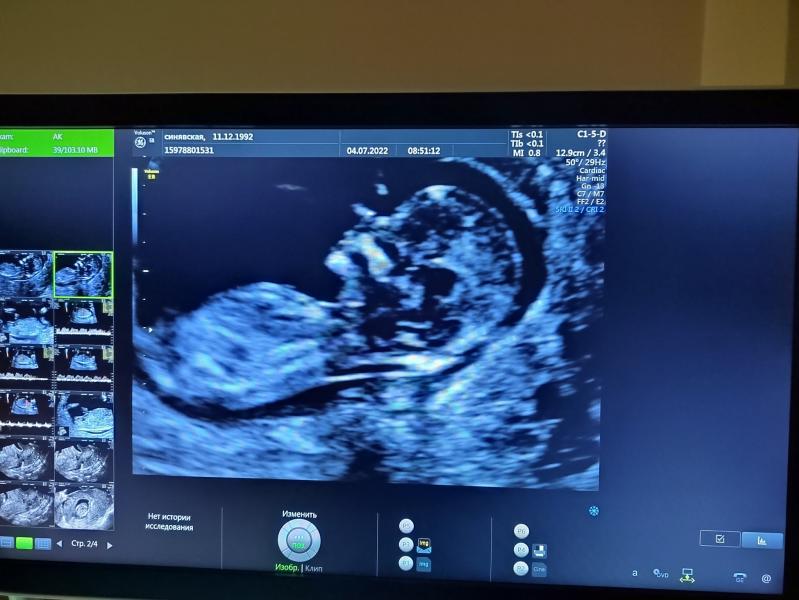

Первый скрининг 04.07.2022: все хорошо! Как я волновалась без мужа у кабинета врача

04.07.2022 был наш первый скрининг😁 Радует, что всё хорошо🙏❤️ Без мужа наверное я бы с ума сошла от волнения перед дверью кабинета🤪